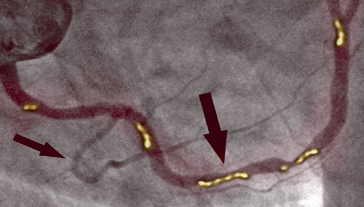

PRED

Na sliki levo vidimo zoženje desne koronarne arterije pri 66-letnem moškem. Vidno je znatno zoženje v proksimalnem odseku, ki ga povzroča poapnela aterosklerotična leha in ki ovira pretok krvi.